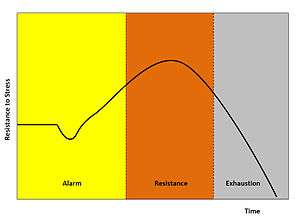

General adaptation syndrome

Physiologists define stress as how the body reacts to a stressor, real or imagined, a stimulus that causes stress. Acute stressors affect an organism in the short term; chronic stressors over the longer term. General Adaptation Syndrome (GAS), developed by Hans Selye, is a profile of how organisms respond to stress; GAS is characterized by three phases: a nonspecific mobilization phase, which promotes sympathetic nervous system activity; a resistance phase, during which the organism makes efforts to cope with the threat; and an exhaustion phase, which occurs if the organism fails to overcome the threat and depletes its physiological resources.[82]

Alarm is the first stage, which is divided into two phases: the shock phase and the antishock phase.[83]

- Shock phase: During this phase, the body can endure changes such as hypovolemia, hypoosmolarity, hyponatremia, hypochloremia, hypoglycemia—the stressor effect. This phase resembles Addison's disease. The organism's resistance to the stressor drops temporarily below the normal range and some level of shock (e.g. circulatory shock) may be experienced.

- Antishock phase: When the threat or stressor is identified or realized, the body starts to respond and is in a state of alarm. During this stage, the locus coeruleus/sympathetic nervous system is activated and catecholamines such as adrenaline are being produced, hence the fight-or-flight response. The result is: increased muscular tonus, increased blood pressure due to peripheral vasoconstriction and tachycardia, and increased glucose in blood. There is also some activation of the HPA axis, producing glucocorticoids (cortisol, aka the S-hormone or stress-hormone).

Stage 2

Resistance is the second stage and increased secretion of glucocorticoids play a major role, intensifying the systemic response—they have lipolytic, catabolic and antianabolic effects: increased glucose, fat and aminoacid/protein concentration in blood. Moreover, they cause lymphocytopenia, eosinopenia, neutrophilia and polycythemia. In high doses, cortisol begins to act as a mineralocorticoid (aldosterone) and brings the body to a state similar to hyperaldosteronism. If the stressor persists, it becomes necessary to attempt some means of coping with the stress. Although the body begins to try to adapt to the strains or demands of the environment, the body cannot keep this up indefinitely, so its resources are gradually depleted.

Stage 3

The third stage could be either exhaustion or recovery:

- Recovery stage follows when the system's compensation mechanisms have successfully overcome the stressor effect (or have completely eliminated the factor which caused the stress). The high glucose, fat and aminoacid levels in blood prove useful for anabolic reactions, restoration of homeostasis and regeneration of cells.

- Exhaustion is the alternative third stage in the GAS model. At this point, all of the body's resources are eventually depleted and the body is unable to maintain normal function. The initial autonomic nervous system symptoms may reappear (sweating, raised heart rate, etc.). If stage three is extended, long-term damage may result (prolonged vasoconstriction results in ischemia which in turn leads to cell necrosis), as the body's immune system becomes exhausted, and bodily functions become impaired, resulting in decompensation.

The result can manifest itself in obvious illnesses, such as peptic ulcer and general trouble with the digestive system (e.g. occult bleeding, melena, constipation/obstipation), diabetes, or even cardiovascular problems (angina pectoris), along with clinical depression and other mental illnesses.